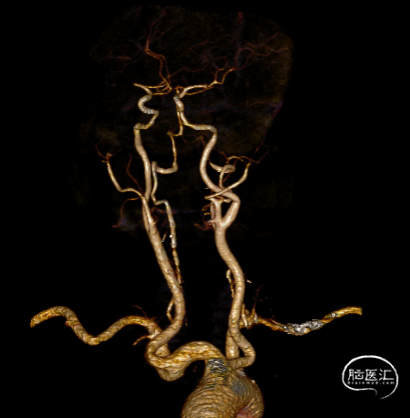

局麻,右股动脉入路置8F短鞘,导管导丝技术将8F MPA置于右C1末端,造影确认右M1急性闭塞,侧支代偿差。

以Transend-14导丝 + Headway21导管到达M1中段,Sofia Plus顺畅到位(M1中段),ADATP技术抽吸取栓,一次成功取通,前向血流TICI 3级,无栓子逃逸及原位狭窄,穿刺至开通时间仅用时9min。

DSA造影见右侧大脑中动脉M1中段以远闭塞,ACA向MCA区域仅少量代偿。Sofia Plus在Headway21导管及Transend导丝引导下,很顺畅通过虹吸段等部位,到达M1中段。

采用ADAPT技术,血流快速复通;最右图为Sofia Plus导管前端及取出血栓。

以Transend导丝 + Headway21导管到达M1中段,Sofia PLUS顺畅到位(M1中段),ADATP技术抽吸取栓,一次成功取通,前向血流恢复至TICI3级,无栓子逃逸及原位狭窄,穿刺至开通时间20min(患者术中间断躁动不配合)。

以Sofia Plus进行抽吸取栓1次(ADAPT技术),实现血流复通(TICI 3级)